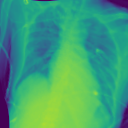

Additionally, we evaluate the performance of DiffeoNN on real-world data, using a dataset with chest X-ray images and their ground-truth lung segmentation from (RSUA, 2023). The original dataset contains images and corresponding ground-truth segmentations into three different classes (“Non-Covid”, “Covid”, and “Non-Covid-Pneumonia”). We combine the images and corresponding ground-truth segmentations of the initial three classes into one dataset, which is then split into a training dataset of image-segmentation pairs, a validation dataset of pairs, and a test dataset of pairs. We then proceed as in Section 4.1.1 to create a dataset of diffeomorphically transformed images.

We apply DiffeoNN, the inner U-Net (naïve approach) and an augmented U-Net, which is trained on the original and the diffeomorphically transformed training dataset, to the diffeomorphically transformed images from the test dataset. Visual results are presented in Figure 4 and further details on the experimental setup, training, and additional examples in Appendix B. The results closely mirror those obtained on the synthetic dataset, see Table 1(b). On average, DiffeoNN outperforms the naïve approach, validating the effectiveness of our approach. The canonicalisation step pushes the input image towards the training dataset by moving the thorax to a more central position and aligning the shoulders, which makes it easier for the inner U-Net to predict an accurate lung segmentation. While our method performs slightly below the augmented gold-standard baseline, it offers more flexibility by not relying on data augmentation or retraining, making it a practical and robust solution in real-world applications.

| Input | Canonicalised Input | Segmentation of | Output DiffeoNN | Output Naïve U-Net | Output Augmented U-Net | Ground-Truth Segmentation |